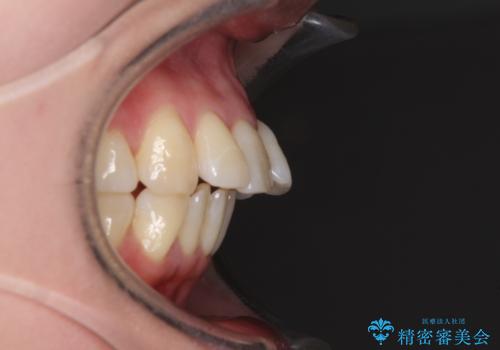

- 上の前歯の出っ歯を治したいとのことで来院された患者様です。

後戻りによる再矯正というもともあり、インビザラインを希望されていました。

上顎の歯は後方移動とIPR(歯と歯の間を削る)によって口元が引っ込むように、下顎は歯列全体の拡大とIPRによって上顎とバランスよく咬み合うように設計し、インビザラインにより治療を行うこととしました。

治療を開始して暫くして、勤務先から2年以上帰国することができず、それまでの移動がほとんど後戻りしてしまい、帰国後に再度後戻りをリカバリーするための治療を行うこととなりました。

5年以上の治療期間がかかりましたが、気になっている部分を改善することができました。